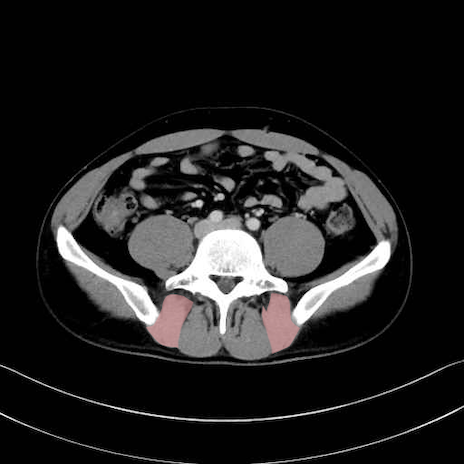

外閉鎖筋 (Obturator externus)